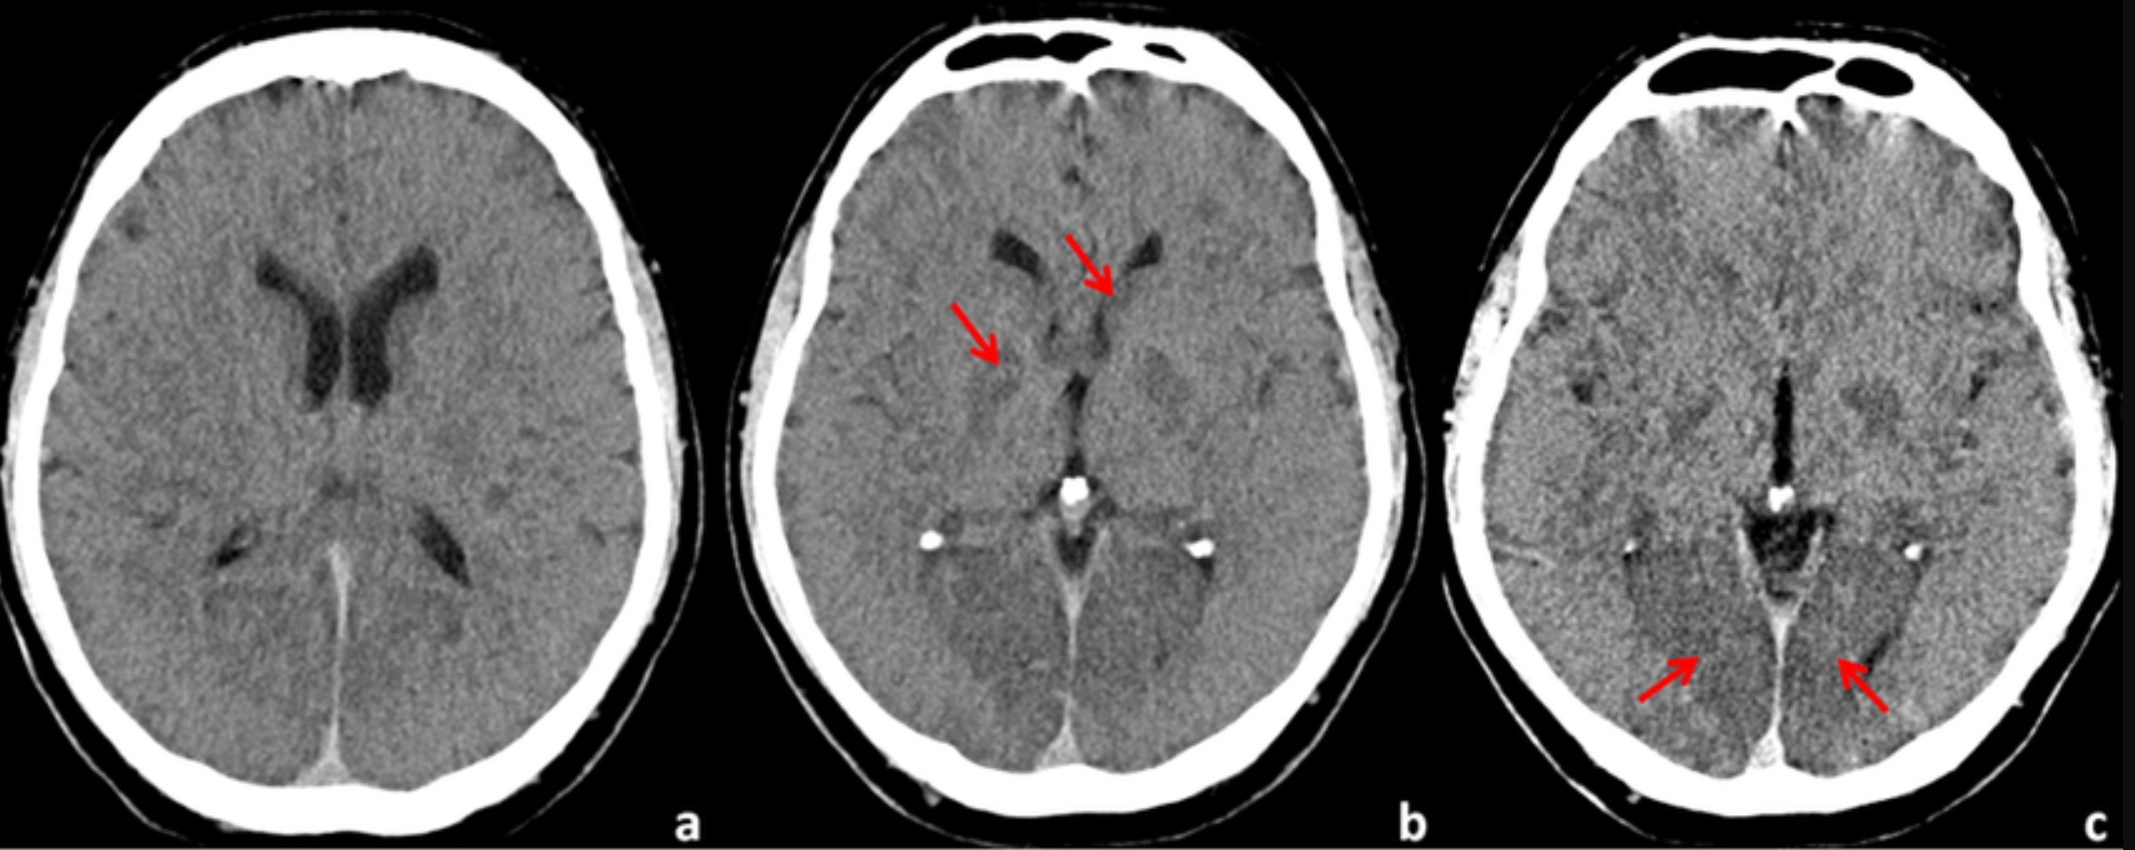

脑动脉高密度征(动脉致密征)

此征象出现时间最早(高级考点),发病1小时内就可出现。其表现为病变同侧M1段呈现条状高密度影,M2或M3处出现点状高密度点。不过,该征象的出现概率较低,容易发生漏诊情况。为进一步确认,可借助 CTA 来证实相应动脉是否闭塞。